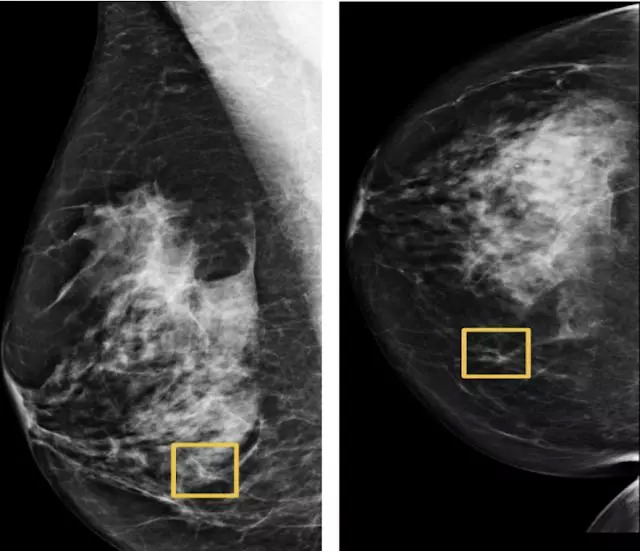

- 针对乳房X线照相术的深度学习模型可以帮助医生发现乳腺癌;